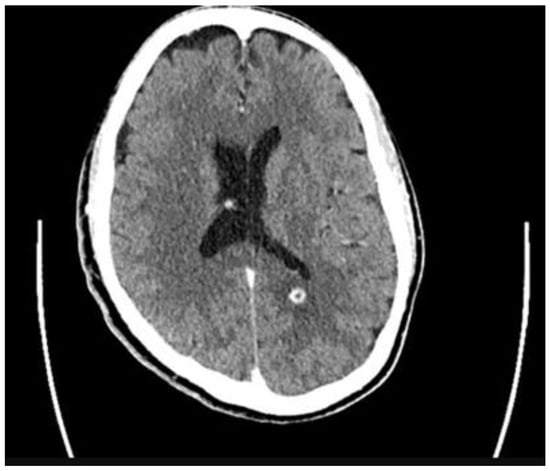

2. Case